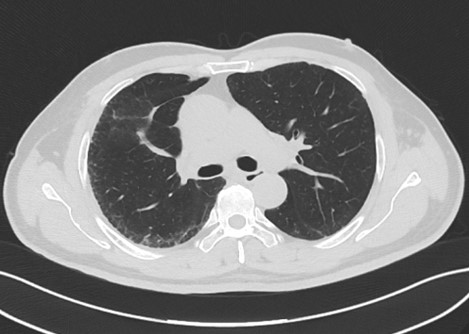

皮膚過敏,相信大家都深有體會(huì)或了解,但你是否聽過肺也會(huì)“過敏”呢?而且,慢性過敏性肺炎危害很大,今天,福建省福州肺科醫(yī)院間質(zhì)肺規(guī)范化診療中心就帶大家揭開“肺過敏的神秘面紗”,一起認(rèn)識(shí)生活中形形色色的過敏原。下面我們介紹近期幾例纖維化型過敏性肺炎,提高大家對(duì)生活中長(zhǎng)見過敏原的認(rèn)識(shí)。

過敏原無處不在,但又很隱匿,宿主的易感性也不一樣。過敏性肺炎早發(fā)現(xiàn)、脫離環(huán)境就可以治愈,但是由于患者經(jīng)常未及時(shí)發(fā)現(xiàn)過敏原,對(duì)于早期肺部比較典型的影像特征也缺乏足夠的敏感性,仍繼續(xù)暴露在過敏環(huán)境中,最后發(fā)展成纖維化型過敏性肺炎。我院間質(zhì)肺規(guī)范化診療中心將盡可能詳盡地采集病史以發(fā)現(xiàn)可能存在的環(huán)境暴露因素以及時(shí)間軸關(guān)系,發(fā)揮多學(xué)科診療優(yōu)勢(shì),早發(fā)現(xiàn)早診斷,助力患者盡快脫離過敏原,避免不可逆的肺纖維化。

五、纖維化性過敏性肺炎的危害和治療

過敏性肺炎診療相關(guān)經(jīng)驗(yàn)嚴(yán)重缺乏,不同地區(qū)臨床實(shí)踐存在很大差異,纖維化/慢性過敏性肺炎很可能被誤診為特發(fā)性肺纖維化或其他特發(fā)性間質(zhì)性肺炎。自1700年發(fā)現(xiàn)間質(zhì)性肺炎以來,許多致敏原被證實(shí)與其有關(guān),但仍有約60%的患者即使有詳細(xì)的病史也無法確定潛在的致敏原。纖維化性間質(zhì)性肺炎如果不治療對(duì)身體危害極大,可繼發(fā)呼吸衰竭、肺動(dòng)脈高壓、肺大泡、自發(fā)性氣胸等。早期診斷和避免接觸過敏原是治療的關(guān)鍵。對(duì)激素和/或免疫調(diào)節(jié)劑治療無反應(yīng)的進(jìn)展性患者,只能考慮肺移植。